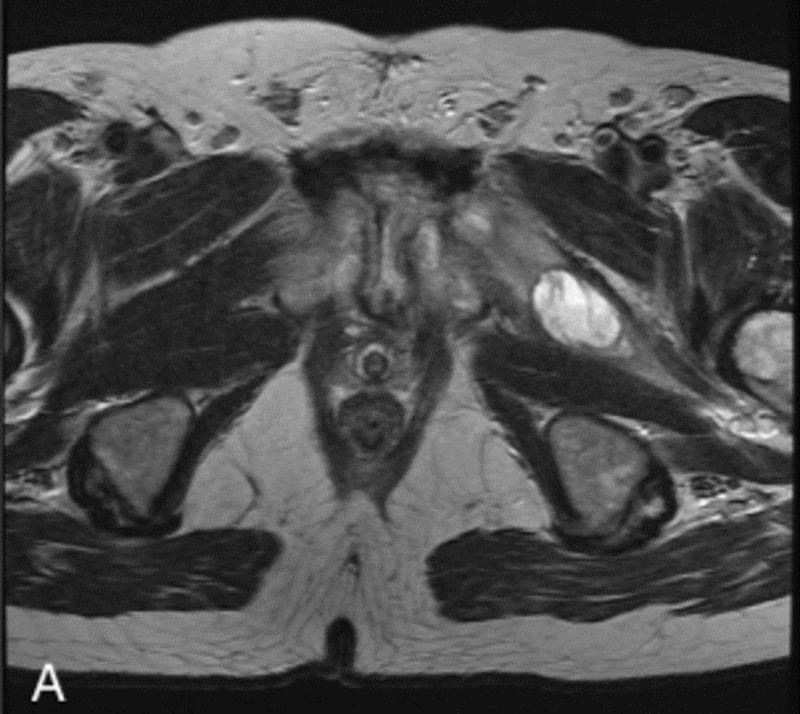

腰椎MRI,L2和L3椎体强化,骨髓水肿,伴椎前/椎旁软组织肿胀,弥漫性椎间盘膨出,黄韧带增厚,椎管狭窄

腰椎MRI,L2/3明显狭窄,左侧明显,伴椎间盘炎和中度硬膜囊压迫,周围可见软组织水肿,左侧腰大肌轻度水肿。